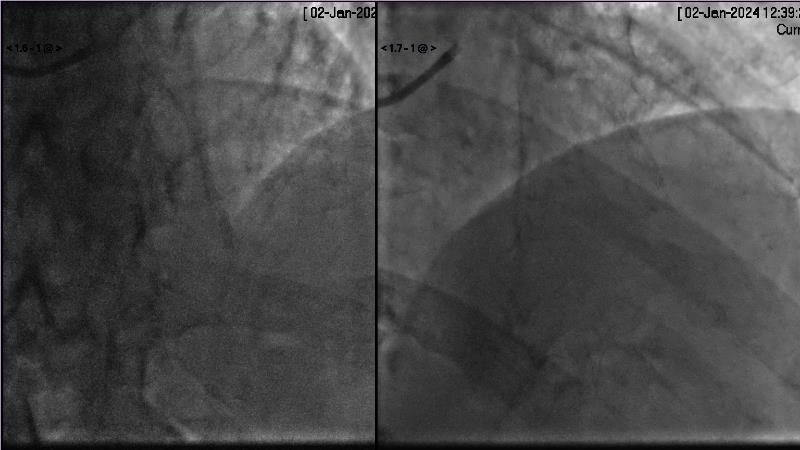

Browse this EuroPCR 2024 session to explore the safety and efficacy of sirolimus-coated balloons from pre-clinical data, review MagicTouch data from real-world populations with case-based examples, and learn about the MagicTouch sirolimus-coated balloon clinical programs. Discover insights and takeaways from the significance of the EASTBOURNE subgroups, and analyze the challenges and opportunities in PCI for diabetic patients.